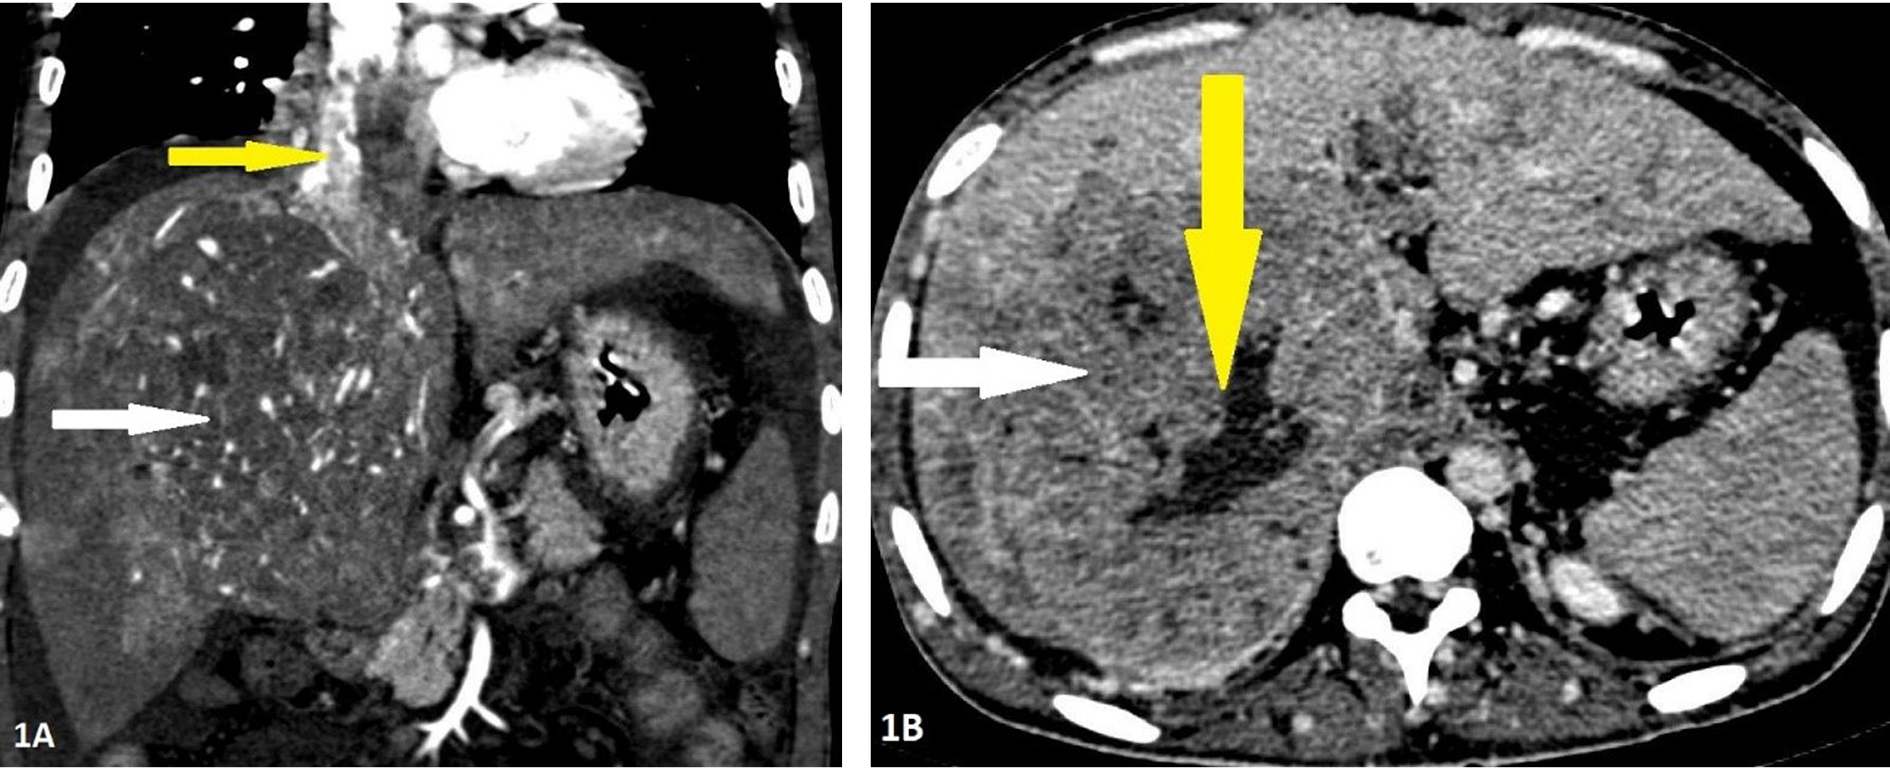

His blood tests for hepatitis B virus (HBV) surface antigen, hepatitis B virus (HBV) core IgM antibodies, hepatitis C virus (HCV) antibodies, and human immunodeficiency virus (HIV) type 1 (HIV-1) p24 antigen and HIV-1 and HIV-2 antibodies were negative. Other laboratory results (normal ranges in parentheses) were as follows: Haemoglobin, 9.4 gm/dl (12–15 gm/dl); total bilirubin, 12 mg/dl (0.2–1.2 mg/dl); aspartate aminotransferase, 376 IU/l (5–40 IU/l); alanine aminotransferase, 114 IU/l (5–47 IU/l); alkaline phosphatase, 444 IU/l (111–295 IU/l); and lactate dehydrogenase, 229 IU/l (100–225 IU/l). Ultrasonography of the abdomen revealed a large space-occupying lesion in the right lobe of the liver with the background of chronic parenchymal liver disease and portal vein thrombosis. Contrast Enhanced Computed Tomography (CECT) abdomen reveals an 11.9 × 10.8 × 14 cm hypervascular mass showing enhancement on arterial phase and rapid washout in the right lobe of liver with thrombus extending into IVC and portal vein (Figure 1). The serum α-fetoprotein (AFP) was elevated to > 54000 ng/ml (normal range <13.2 ng/ml). His electrocardiography showed normal sinus rhythm and chest X-ray showed mild right-sided pleural effusion and normal cardiothoracic ratio. A 2D transthoracic echocardiogram demonstrated a large intracardiac right atrial thrombus measuring 5.7 × 2.4 cm obstructing the tricuspid valve during the diastolic phase of the cardiac cycle (Figure 2).

Figure 1. Contrast enhanced computed tomography of 32-years-old male with Hepatocellular carcinoma in the right lobe. Panel 1A: Arterial phase imaging in coronal reconstruction showing the mass having internal areas of arterial hyperenhancement (white arrow) with enhancing tumoral thrombus in the inferior vena cava and right atrium (yellow arrow). Panel 1B: Portal phase imaging in axial section showing washout of contrast in the lesion (white arrow) with central area of nonenhancement suggestive of necrosis (yellow arrow).